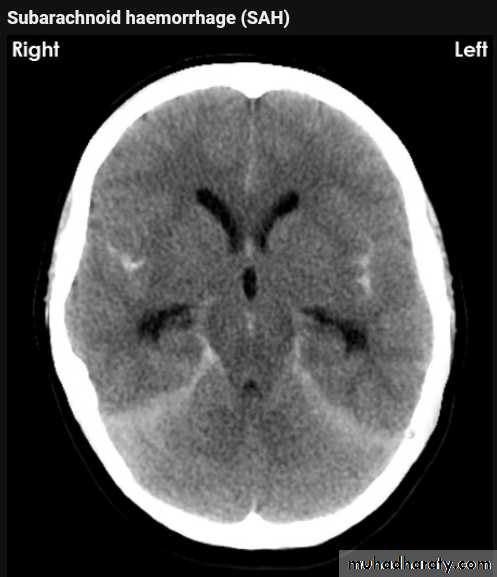

Subarachnoid hemorrhage

causesdue to ruptured aneurysm over 90 % of cases spcially at the circle of Willis .

ruptured AV malformation .

trauma .

CT finding

hyper density is seen within the SAS ( hyperdense sulci , being filled with clotted blood)

opacified inter hemispheric fissure ( become white & more dense )

opacification of the falx cerebri .

SAH

White sulciOpacified IHF